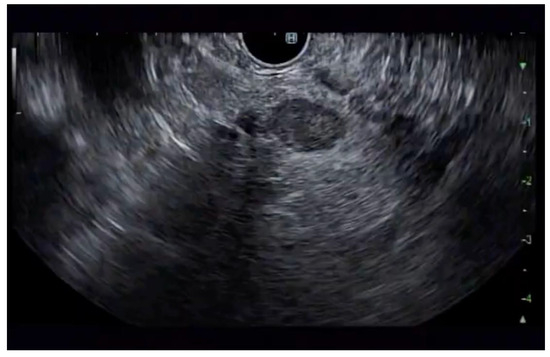

Additional notable cases in our series included a pancreatic cyst with a high-grade dysplastic nodule in an 80-year-old female patient. The initial 11.0 × 10.0 mm nodule was completely ablated (0.0 × 0.0 mm residual) after a single RFA session using a 19-gauge/7 mm needle at 50 watts of power for three applications with no complications (Figure 1, Figure 2 and Figure 3). Similarly, a 41-year-old male with a 13.5 × 8.5 mm insulinoma in the pancreatic neck who presented with multiple syncopal episodes secondary to hypoglycemia achieved complete radiologic and biochemical resolution after a single RFA session using a 19-gauge/5 mm needle at 10 watts of power for two applications (Figure 4, Figure 5 and Figure 6), with no adverse events and normalization of his insulin and glucose levels post-procedure and the resolution of his syncope.

Figure 4. pNET at the neck of the pancreas (insulinoma) on EUS.

Jcm 14 03958 g004